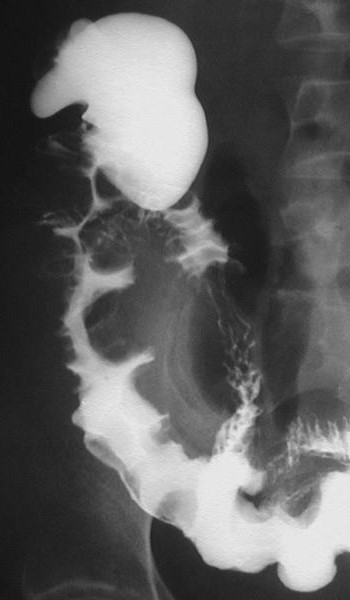

Viêm đại tràng do lao có hình ảnh giống bệnh Crohn, bệnh hiếm ở người da trắng nhưng hay gặp ở người châu Á và bệnh nhân AIDS. Mặc dù phần lớn là thứ phát sau lao phổi, nhưng đa số bệnh nhân không có bằng chứng lao phổi trước đó hoặc lao phổi hoạt động. Với bệnh nhân châu Á, phần lớn bệnh nhân lao ống tiêu hóa là do nuốt trực khuẩn lao bò. Chẩn đoán trực khuẩn kháng axit hoặc u hạt hoại tử bã đậu có độ nhạy thấp (khoảng 32% và 50%, tương ứng) [9]. Với sự hiểu biết tốt hơn về các đặc điểm của viêm lao đại tràng, chẩn đoán sớm bằng chụp cản quang kép là có thể [10]. Các đặc điểm sớm của lao đại tràng là co thắt, tăng tiết, tăng nhu động, tăng sản lympho, các nếp dầy, và các vết loét nông (Hình 18). Các dấu hiệu của viêm lao đại tràng tiến triển khi chụp cản quang kép bao gồm các vết loét ngang (Hình 19), các nốt, các nếp dầy, polyp viêm hoặc sau viêm, hẹp và biến dạng vùng hồi-manh tràng (Hình 20).

Hình 20. Bệnh nhân nữ 41 tuổi. Chụp cản quang kép cho thấy hẹp và biến dạng vùng hồi-manh tràng và đại tràng lên mà không thấy tổn thương niêm mạc hoạt động.